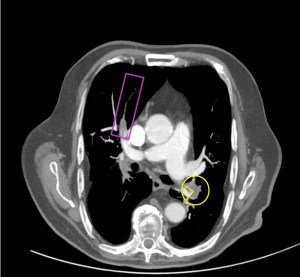

Defecto de repleción parcial periférico con rectificación de la pared de la arteria pulmonar derecha, sugestivo de estigmas de TEP crónico

Estigmas

Defecto de repleción parcial y periférico con ángulo obtuso en arteria lobar inferior derecha (amarillo), sugestivo de TEP crónico. Arteria lobar del LM con aumento de calibre y signo de angulo agudo, sugestivo de TEP agudo. Distal al trombro la arteria segmentaria ha disminuido el calibre por ausencia de flujo (rosa).